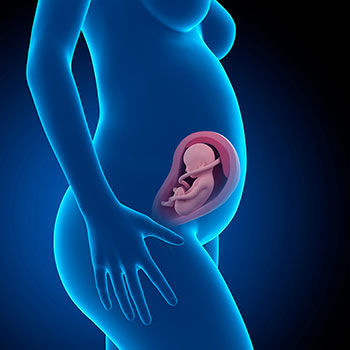

Na 28ª semana de gravidez, o teu bebé mede cerca de 36,6 centímetros e pesa pouco mais de um kilo.

A sua superfície cerebral, que até ao momento era lisa, começa a ter sulcos.

Os cabelos crescem e o seu corpo torna-se mais suave e arredondado, em consequência do aumento do tecido adiposo situado debaixo da pele.

Grávida de 28 semanas

O seu cérebro cresce a um ritmo muito consistente e a transmissão dos impulsos nervosos é assegurada pela mielina, uma substância que reveste os nervos.

O bebé ainda está coberto por uma fina capa de pelugem, o lanugo, que cobre toda a pele exceto as palmas das mãos, as plantas dos pés e o contorno dos lábios.

Os seus sentidos estão cada vez mais despertos. Vais adorar saber que já reconhece a tua voz e que lhe responde, o que também vai acontecer com a música.

Idade do feto: 26 semanas.